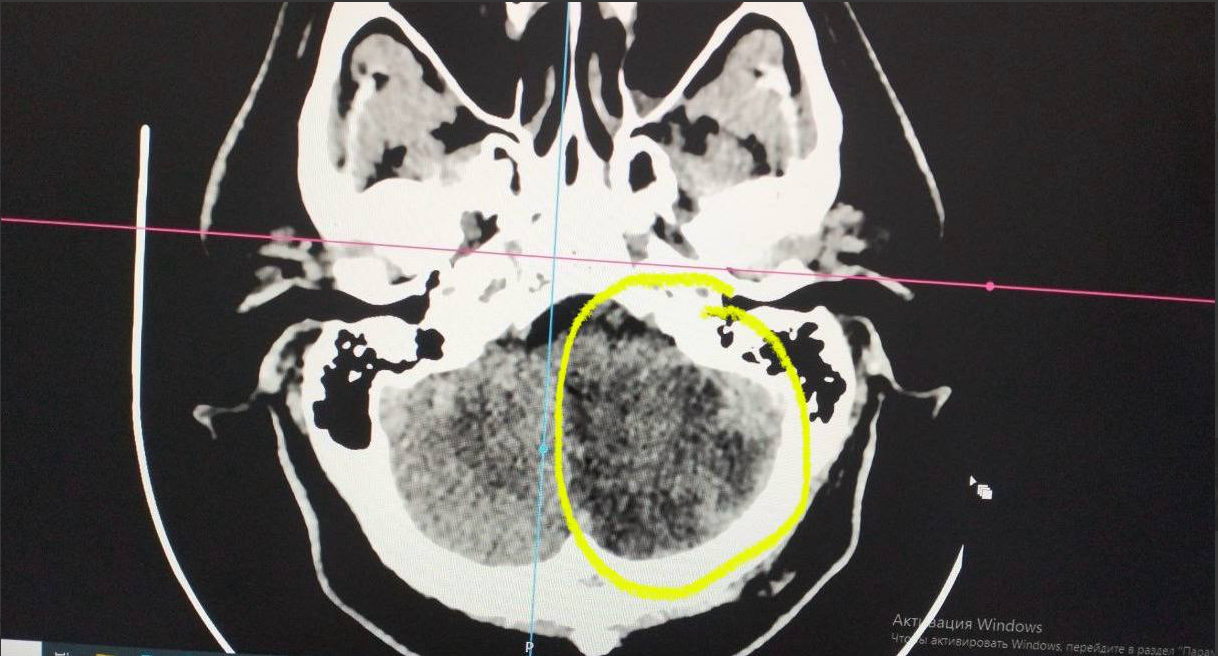

Пациент 1983 года рождения поступил с жалобами — головная боль и высокое давление. Через несколько часов — интенсивное головокружение, неукротимая рвота и диагноз: обширный ишемический инсульт.

💬 "Случай уникален тем, что пациент, имея поражение целого полушария мозжечка, вернулся к полноценной жизни", — отмечает заведующая ПСО №2 Областной больницы №4 Наталия Холмова.